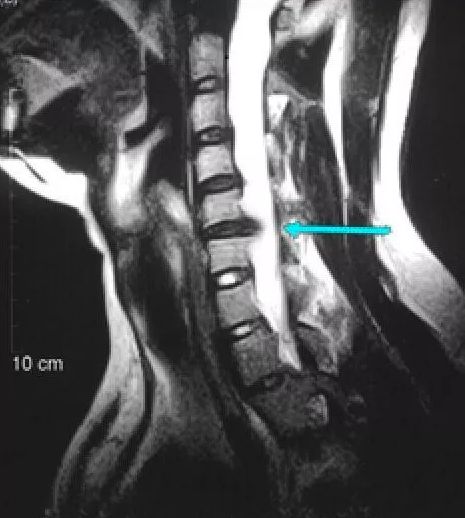

(颈椎间盘突出患者的MRI示意图,可以清晰的看到脊髓受到了严重的压迫)